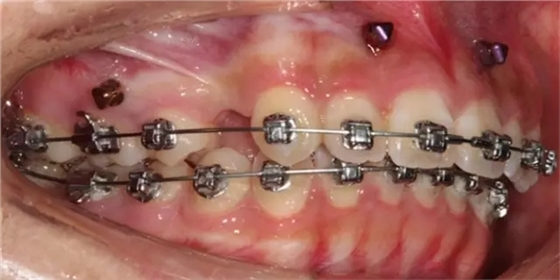

患者側(cè)面凸,鼻唇角較銳,笑時(shí)露齦笑明顯上下牙列擁擠,磨牙尖牙Ⅱ 類關(guān)系,3 度的深覆牙合,上頜中切牙伸長內(nèi)傾拔除上頜雙側(cè)的第一前磨牙,先粘上頜高轉(zhuǎn)矩的自鎖托槽排齊牙列,唇向開展上頜切牙,有一定的覆蓋,粘下頜標(biāo)準(zhǔn)轉(zhuǎn)矩托槽,上頜 1, 2 之間植入種植支抗壓入,同時(shí)后牙 5, 6 之間植入種植支抗內(nèi)收前牙,打開咬合關(guān)閉間隙。治療關(guān)鍵:前牙轉(zhuǎn)矩的控制第 1 個(gè)月 上頜粘上 Damon Q 高轉(zhuǎn)矩托槽,上 .014 熱激活 NiTi 絲。第 3 個(gè)月 上換 .014 x .025 熱激活 NiTi 絲。第 5 個(gè)月 上頜基本排齊,覆蓋增大,上換 .017 x .025 NiTi絲,下頜粘托槽,下 .014 熱激活 NiTi 絲。第 7 個(gè)月 上 .017 x .025 NiTi 絲加搖椅,下?lián)Q .014 x .025 熱激活 NiTi 絲第 9 個(gè)月 上頜換 .019 x .025 NiTi 絲加搖椅,下頜換 .017 x .025 NiTi 絲第 11 個(gè)月 下頜換 .019 x .025 加搖椅,上頜 1, 2 之間, 5, 6 之間植入種植釘,下頜出現(xiàn)散隙。第 13 個(gè)月 上頜換 .019 x .025ss 加搖椅,前牙種植釘用 Power Chain 壓低前牙(每側(cè) 100g),后牙種植釘關(guān)閉間隙(每側(cè) 150g),下?lián)Q .019 x .025ss,Power Chain 關(guān)閉間隙。第 19 個(gè)月 上頜前牙基本壓低到位去除前牙種植釘,繼續(xù)用關(guān)閉間隙,下頜散隙關(guān)閉。

第 22 個(gè)月 上頜覆蓋變小,去除 5, 6 之間種植釘,后牙前移關(guān)閉間隙。第 30 個(gè)月 患者未配合中線牽引,下中線仍有 1mm 右偏,患者對矯治效果滿意要求拆除,拆除固定矯治器,取模制作壓模保持器。 1.骨性 Ⅱ 類的患者內(nèi)收前牙時(shí)需對上頜前牙的轉(zhuǎn)矩進(jìn)行較好的控制才能獲得良好的面型和唇部形態(tài)。 2.露齦笑的患者治療前要分析其病因是唇、牙齦、牙齒、牙槽骨、上頜骨或多種因素結(jié)合,再制定矯治方案。 3.Ⅱ 類第二分類伴露齦笑的患者的上頜前牙移動軌跡是唇向開展-壓低-整體內(nèi)收。 4.Ⅱ 類第二分類牙齒舌傾比較厲害的情況,上頜中切牙慎用樹脂咬合墊。 5.壓低前牙或控根移動時(shí)容易發(fā)生牙根的吸收,需輕力緩慢的移動。